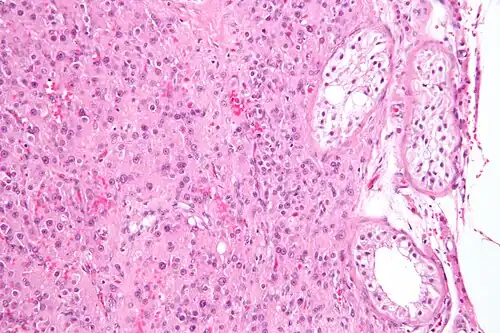

A conclusive diagnosis is made via histology, as part of a pathology report made during or after surgery. Reinke crystals are classically found in these tumours and help confirm the diagnosis, although they are seen in less than half of all Leydig cell tumours. Immunohistochemical markers of Leydig cell tumours include inhibin-alpha, calretinin, and melan-A.[9]

Intermediate magnification micrograph of a Leydig cell tumour. H&E stain. -

High magnification micrograph of a Leydig cell tumour. H&E stain. -